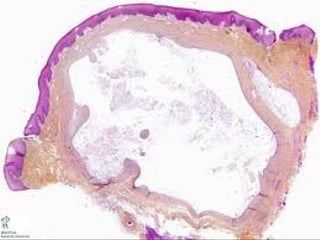

El documento describe la derivación y funciones del tejido epitelial. El tejido epitelial deriva del ectodermo, mesodermo intraembrionario y endodermo intraembrionario. Sus funciones principales son el sostén, protección, absorción, reabsorción, captar estímulos y secreción.